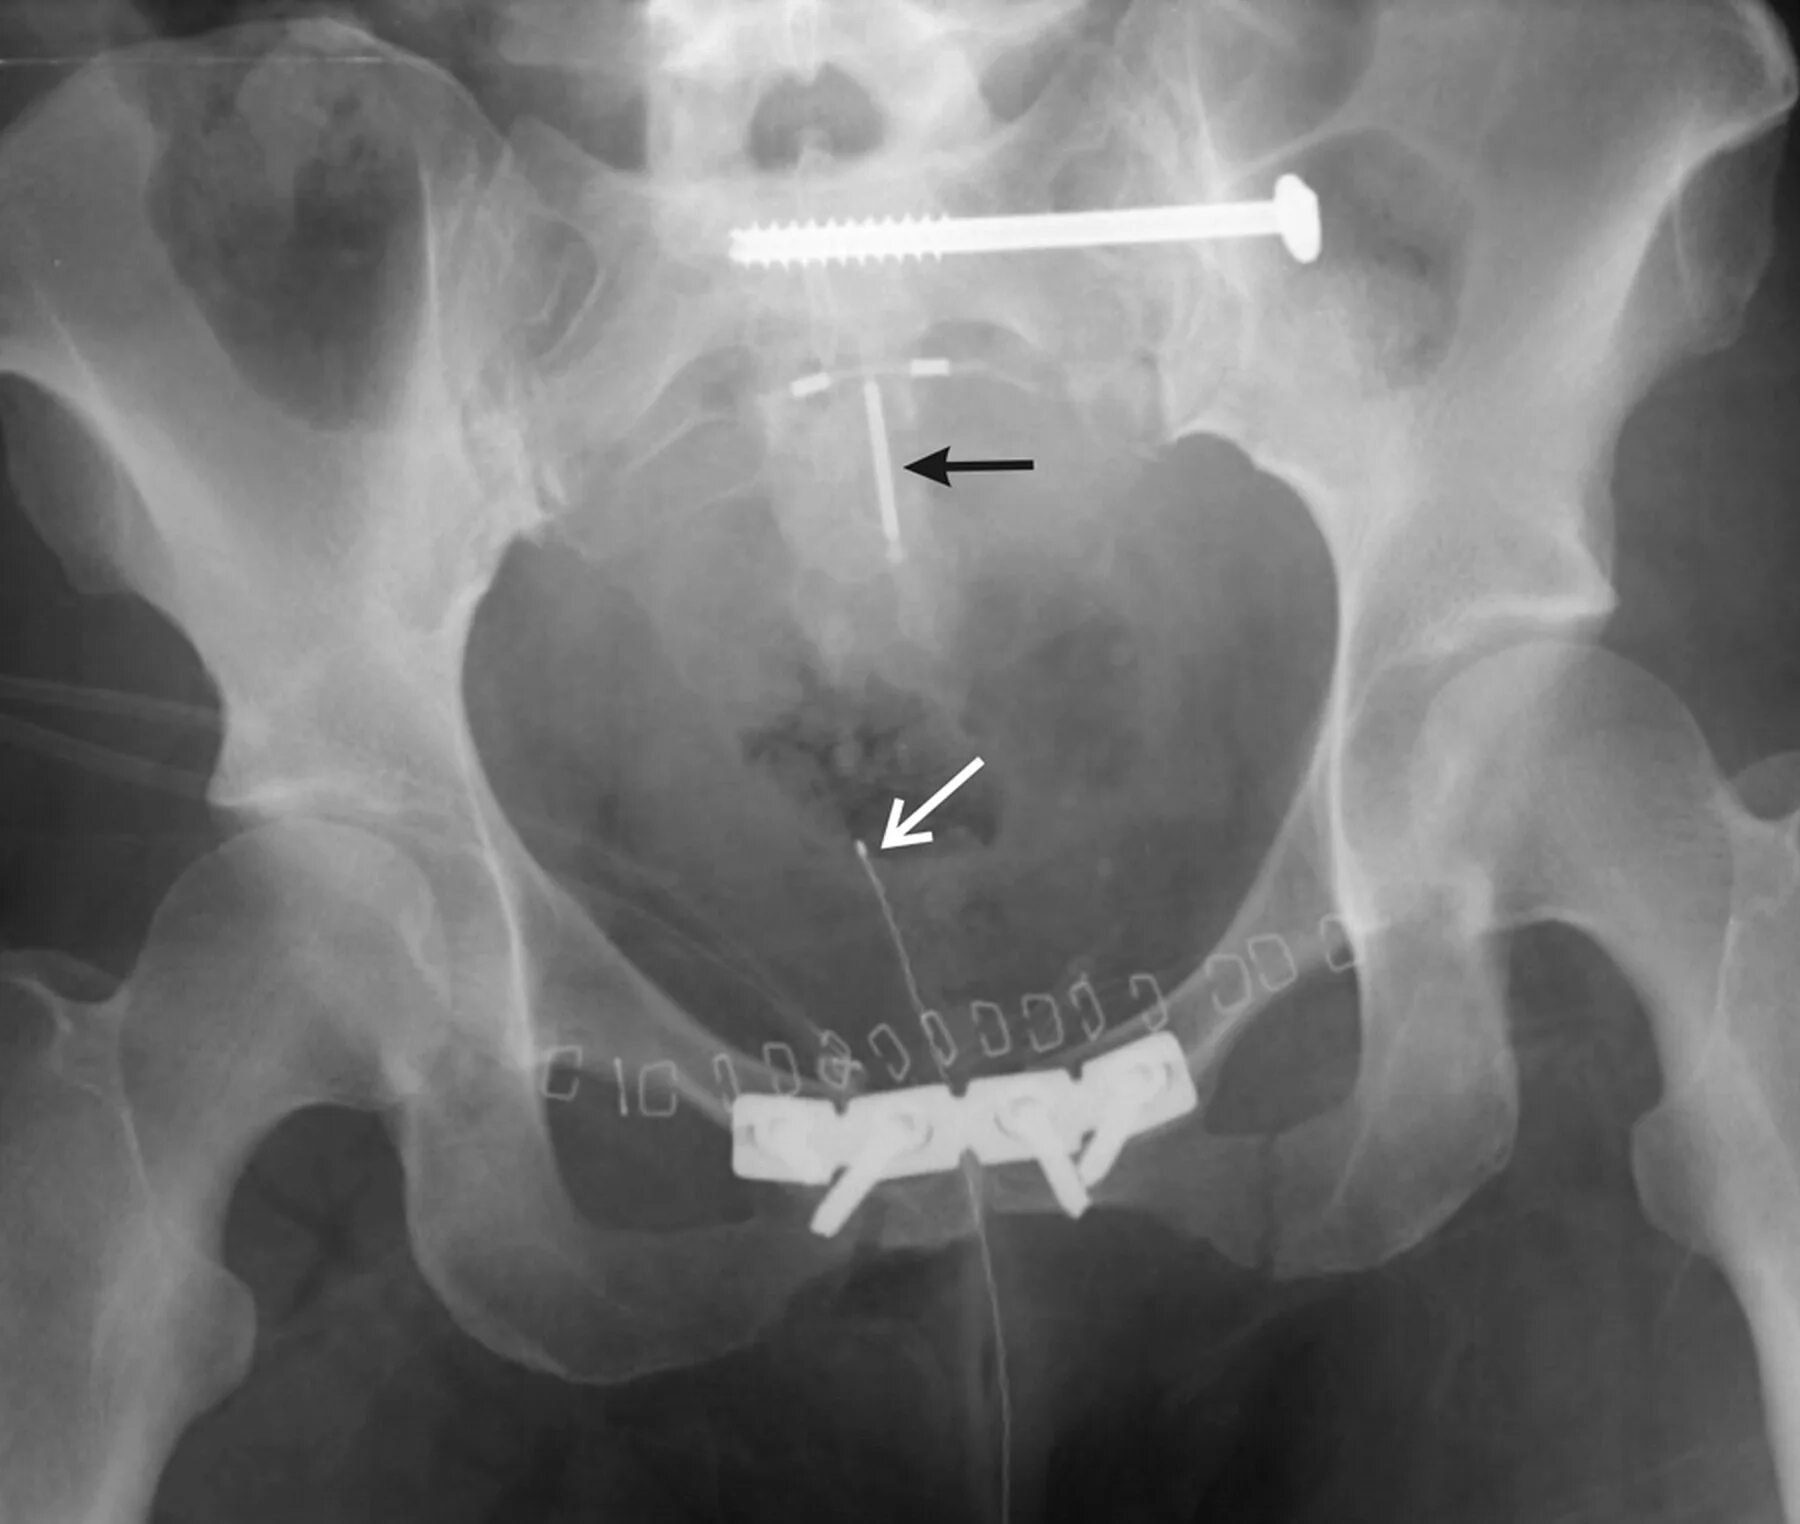

Вмс шейки матки